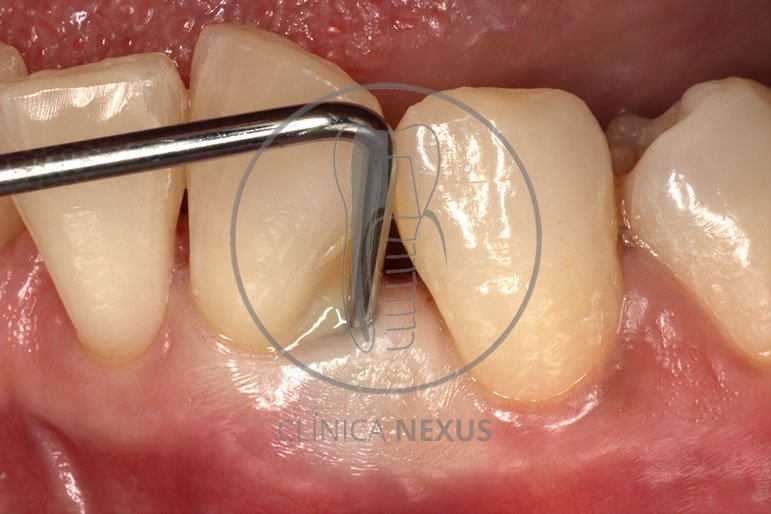

Tratamiento de defectos periodontales infraóseos en sector antero-inferior empleando gel de amelogeninas (Emdogain®) en combinación con un aloinjerto óseo (Biobank®). Paciente de 64 años, sin problemas médicos de relevancia, que presenta una periodontitis leve generalizada, pero asociada a presencia de defectos óseos verticales profundos a nivel de los espacios interdentales entre los caninos y los incisivos laterales inferiores. Tras la pertinente fase higiénica, se llevó a cabo una cirugía periodontal regenerativa, en la que, tras eliminar el cálculo subgingival (factor causal), se empleó una combinación de amelogeninas con un aloinjerto, para promover la regeneración tisular del periodonto perdido. Las imágenes clínicas y radiológicas, al año de seguimiento, reflejan un resultado terapéutico óptimo, con regeneración completa del tejido periodontal y mejora del pronóstico de los dientes involucrados.